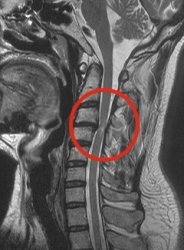

Zur Diagnose dieser

Erkrankung stehen uns verschiedene Untersuchungsmethoden zur Verfügung

wie Röntgen, CT, MRT und die so genannte Myelographie mit denen man

eine Spinalkanaklstenose sichern kann. |